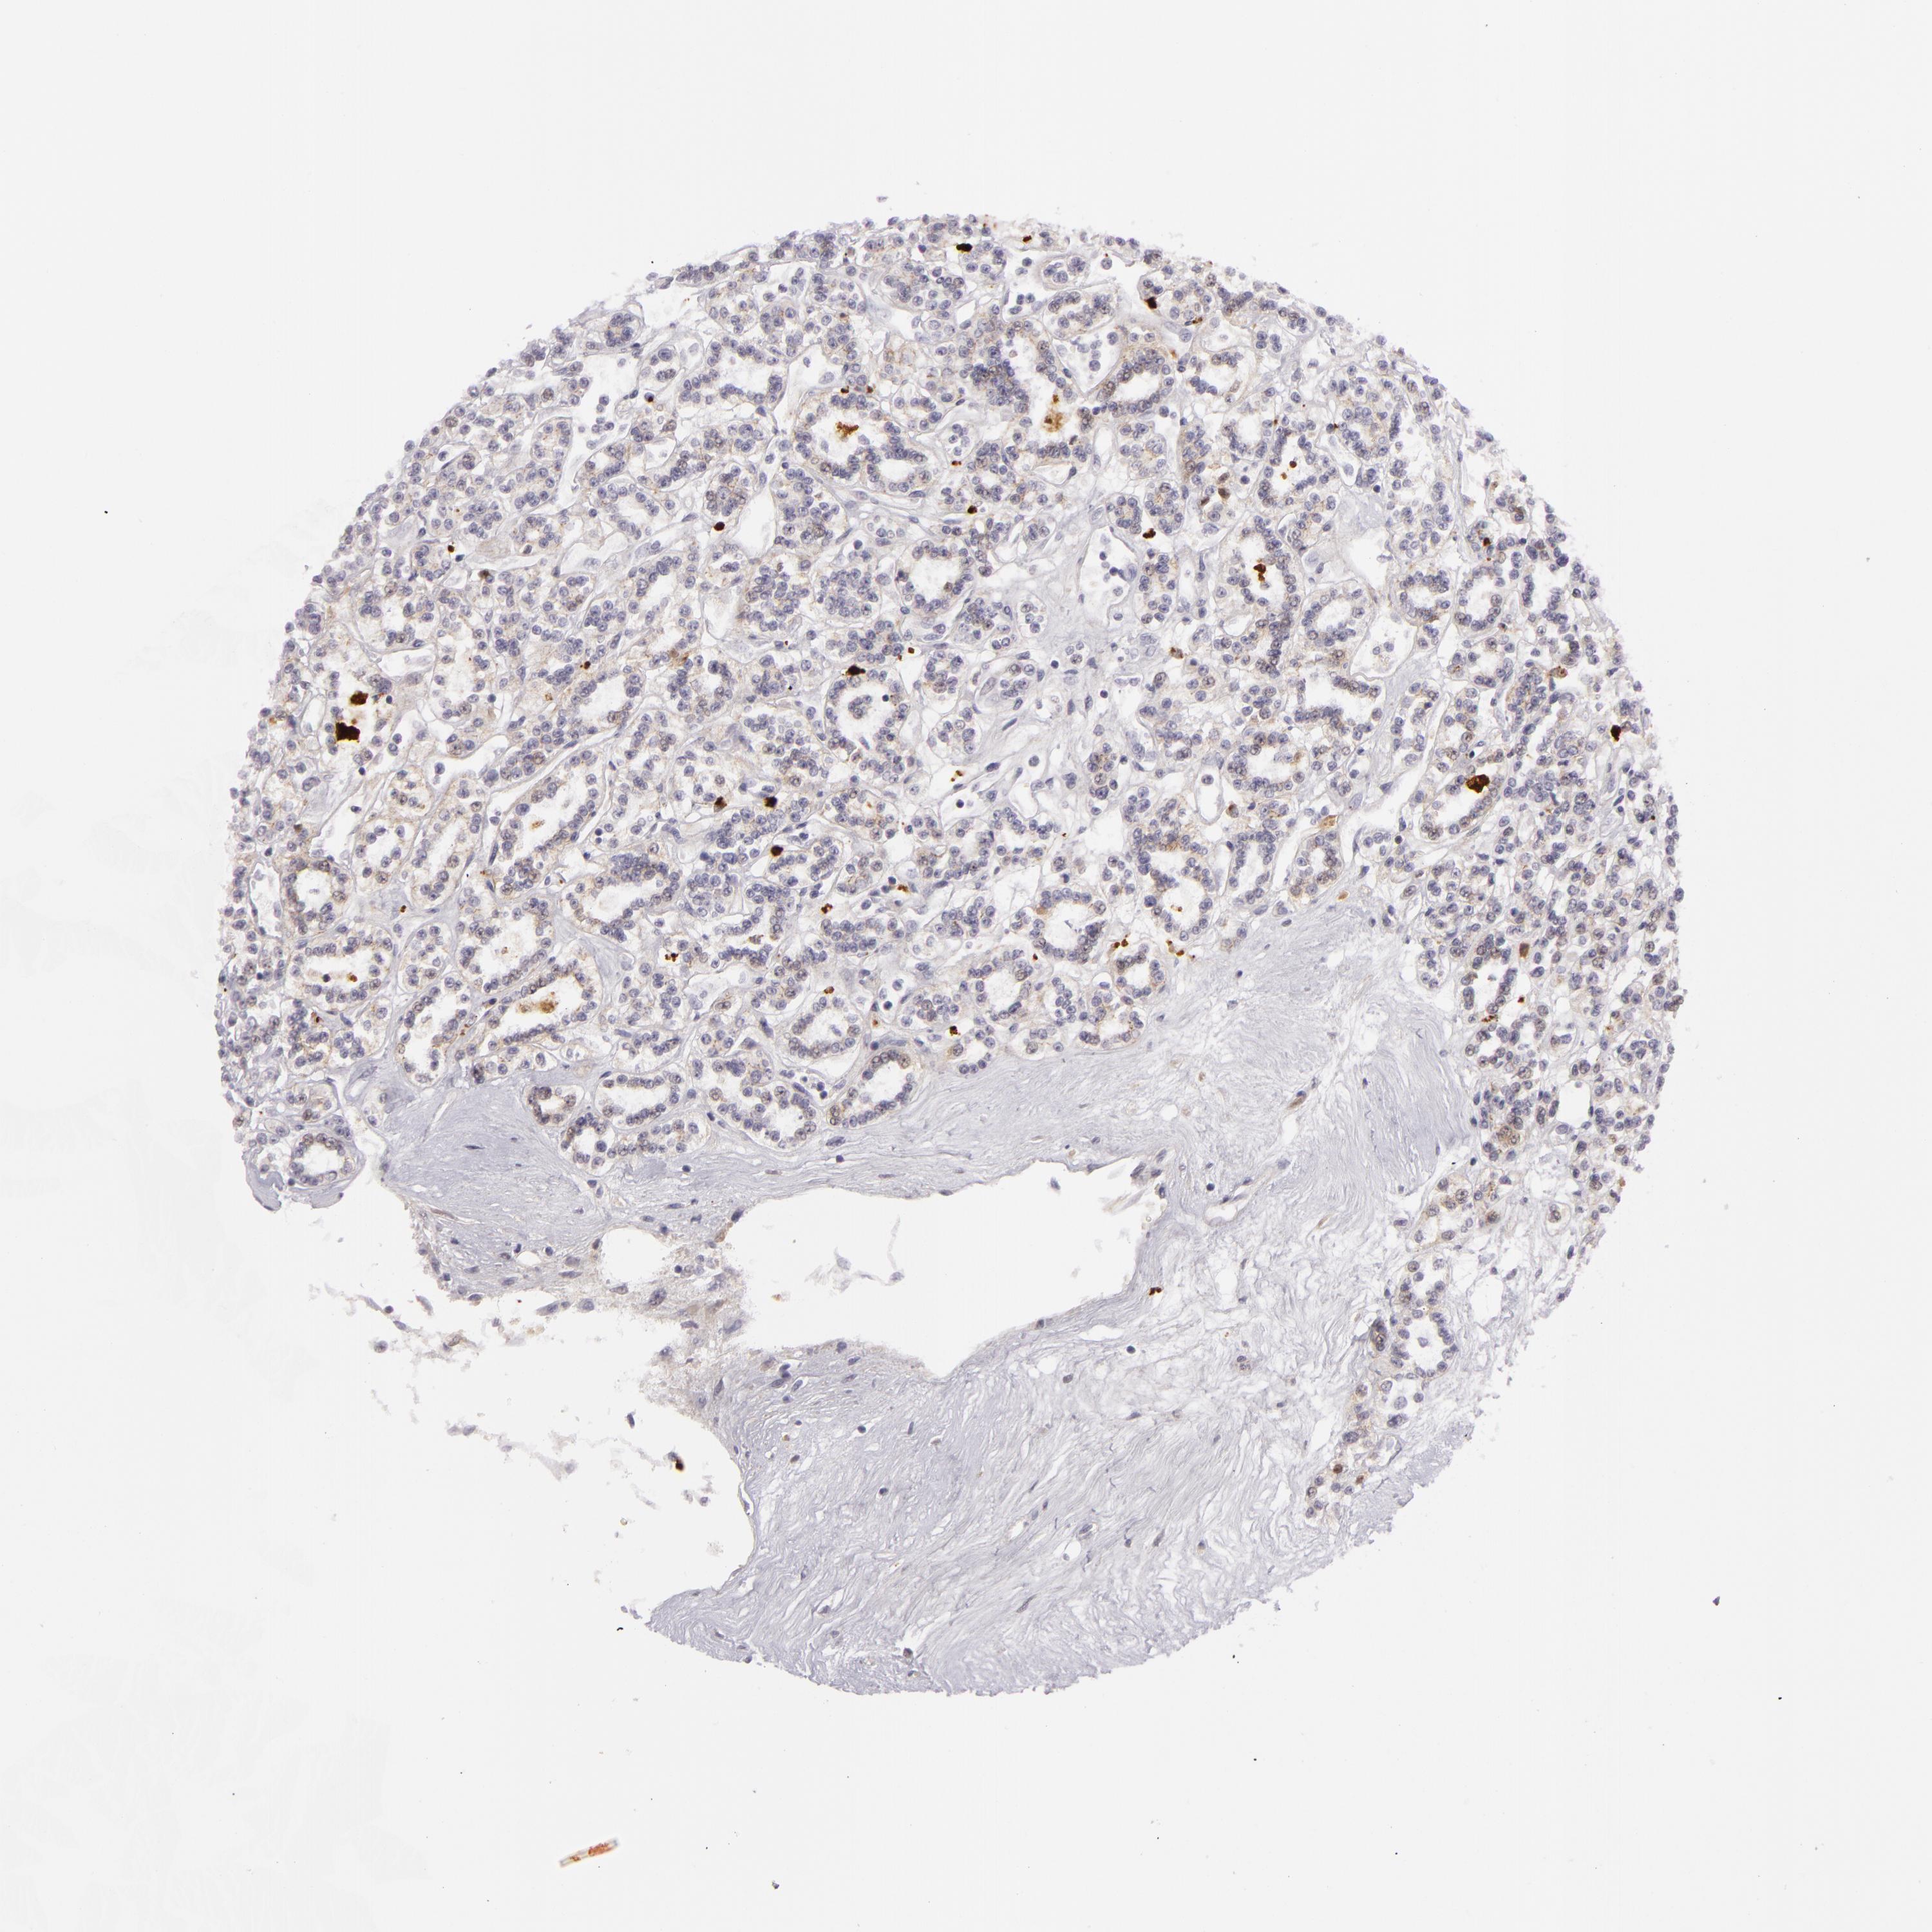

KIDNEY RENAL PAPILLARY CELL CARCINOMA (TCGA) - Interactive survival scatter ploti

The Survival Scatter plot shows the clinical status (i.e. dead or alive) for all individuals in the patient cohort, based on the same data that underlies the corresponding Kaplan-Meier plots. Patients that are alive at last time for follow-up are shown in blue and patients who have died during the study are shown in red.

The x-axis shows the expression levels (FPKM) of the investigated gene in the tumor tissue at the time of diagnosis. The y-axis shows the follow-up time after diagnosis (years). Both axes are complimented with kernel density curves demonstrating the data density over the axes. The top density plot shows the expression levels (FPKM) distribution among dead (red) and alive patients (blue). The right density plot shows the data density of the survived years of dead patients with high and low expression levels respectively, stratified using the cutoff indicated by the vertical dashed line through the Survival Scatter plot. This cutoff is automatically defined based on the FPKM cutoff that minimizes the p-score. The cutoff can be changed by dragging the vertical line or by entering a cutoff value in the square labeled "Current cut-off".

Under the Survival Scatter plot the p-score landscape (black curve; left axis) is shown together with dead median separation (red curve; right axis). Dead median separation is the difference in median mRNA expression between patients who have died with high and low expression, respectively. It is calculated as follows: median FPKM expression of dead patients with high expression - median FPKM expression of dead patients with low expression. This is intended to aid the user in visually exploring custom cutoffs and the associated p-scores and dead median separation.

Individual patient data is displayed and can be filtered by clicking on one or more of the category buttons on the top of the page. Categories describing expression level and patient information include: high, low, alive, dead, female, male and tumor stages. The scale of the x-axis can be toggled between linear and log-scale by clicking on the "x log" button. Mouse-over function shows TCGA ID, patient information and mRNA expression (FPKM) for each patient.

& Survival analysisi